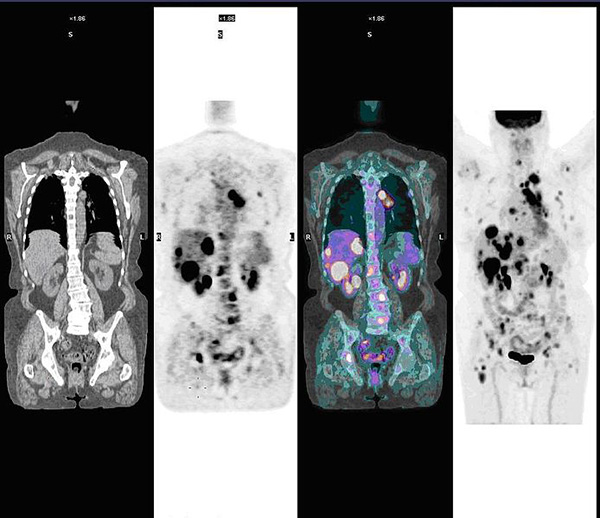

Mathieu Hatt, chercheur au Laboratoire de traitement de l’information médicale (Latim) à Brest vient de recevoir le « Bruce H. Hasegawa Young investigator medical imaging science award ». Ce prix récompense ses travaux au sein de l’équipe « imagerie multimodalité quantitative pour le diagnostic et la thérapie ». De son côté, la société SuperSonic Imagine vient de récolter 50 millions d’euros sur la plateforme Nyse Euronext afin de développer son échographie ultrasonore qui doit « révolutionne l’imagerie médicale »(4).

La recherche et l’innovation mobilisent des financements

L’institut Langevin qui constitue unité Inserm 979 vient par exemple de développer un appareil d’élastographie qui deviendra « outil incontournable ». De même, le Professeur Sigaux, Directeur de la Recherche et de l’Innovation à l’Institut national du cancer suit les travaux de l’Institut national de la santé et de la recherche médicale sur les dépistages précoces du cancer des poumons, et prépare un appel d’offre pour 2015(5). Après la publication obtenue dans la revue médicale anglo-saxonne, Plos One, le chercheur Paul Hoffman s’inquiète de la possibilité « que d’autres équipes s’emparent du projet, notamment en Amérique du Nord ».